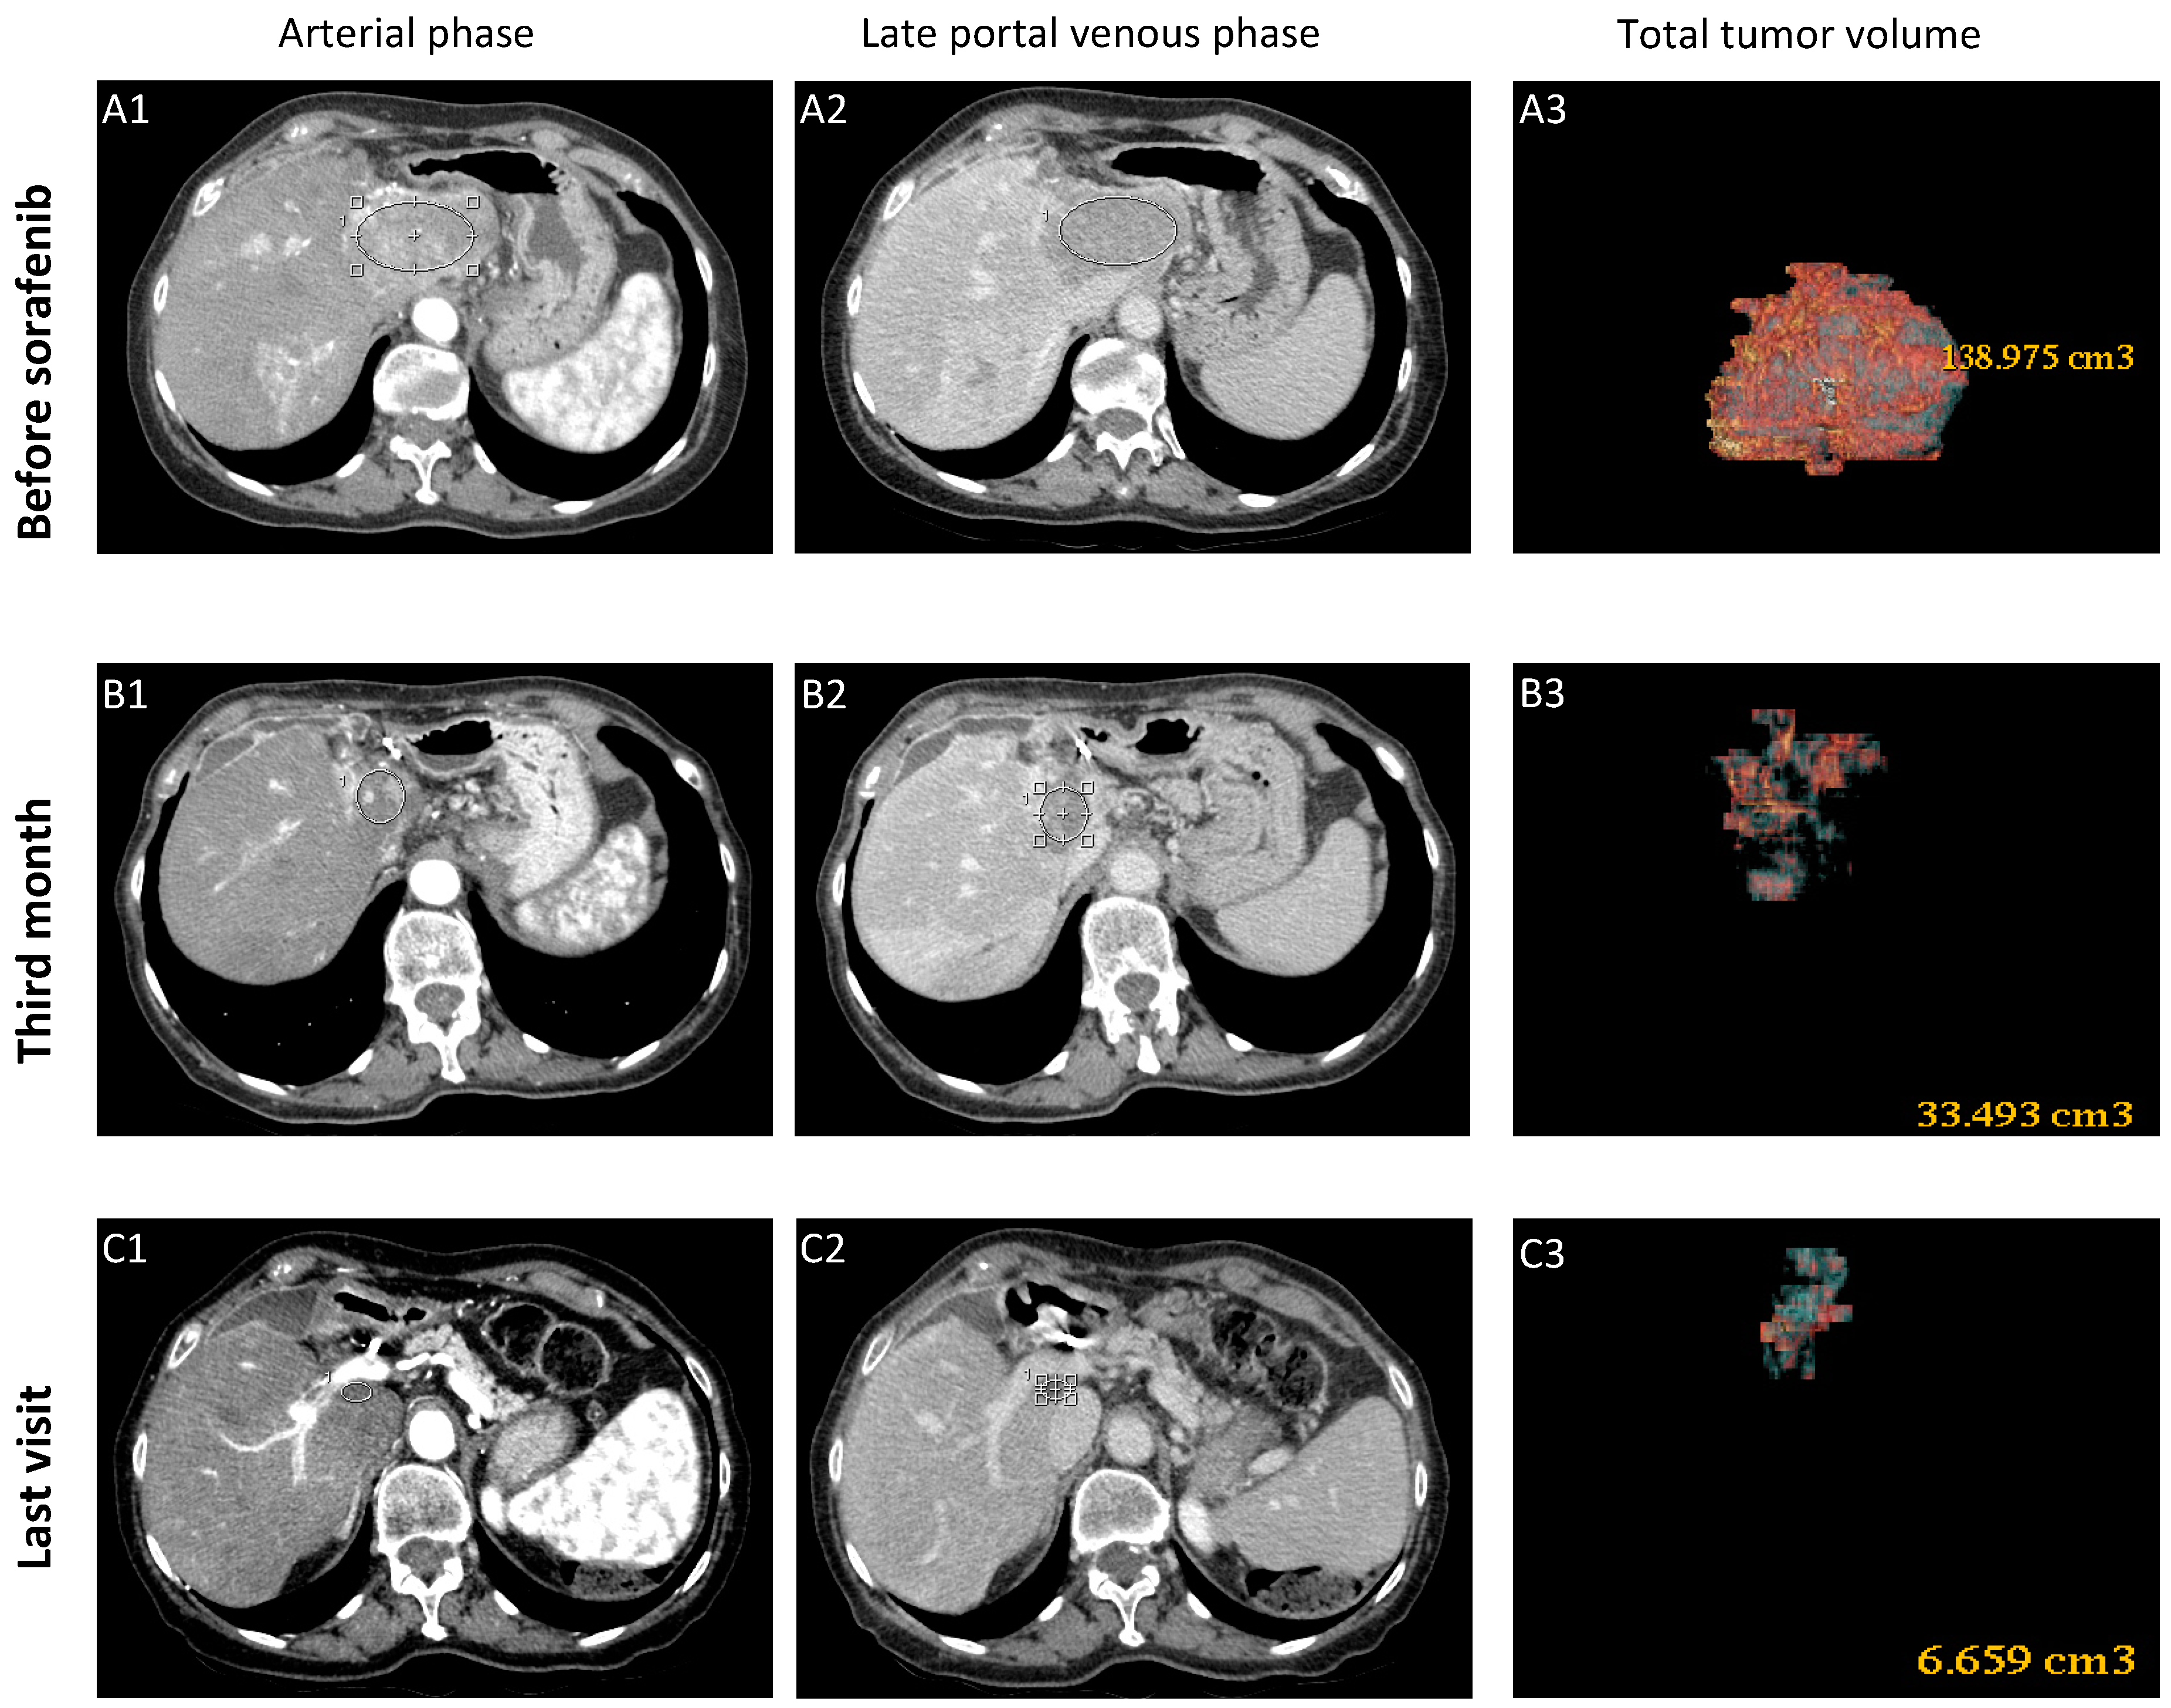

3.1.1. Case-1 (CR to Sorafenib)

| HCC volume (cm3) | 139 | 32 | 52.2 | 6.4 | 24.5 | 6.1 | 200 | 89 | 29.1 | 116 |

| Target Response * | CR | PR | PR | CR | CR | CR | SD | SD | PD | PD |